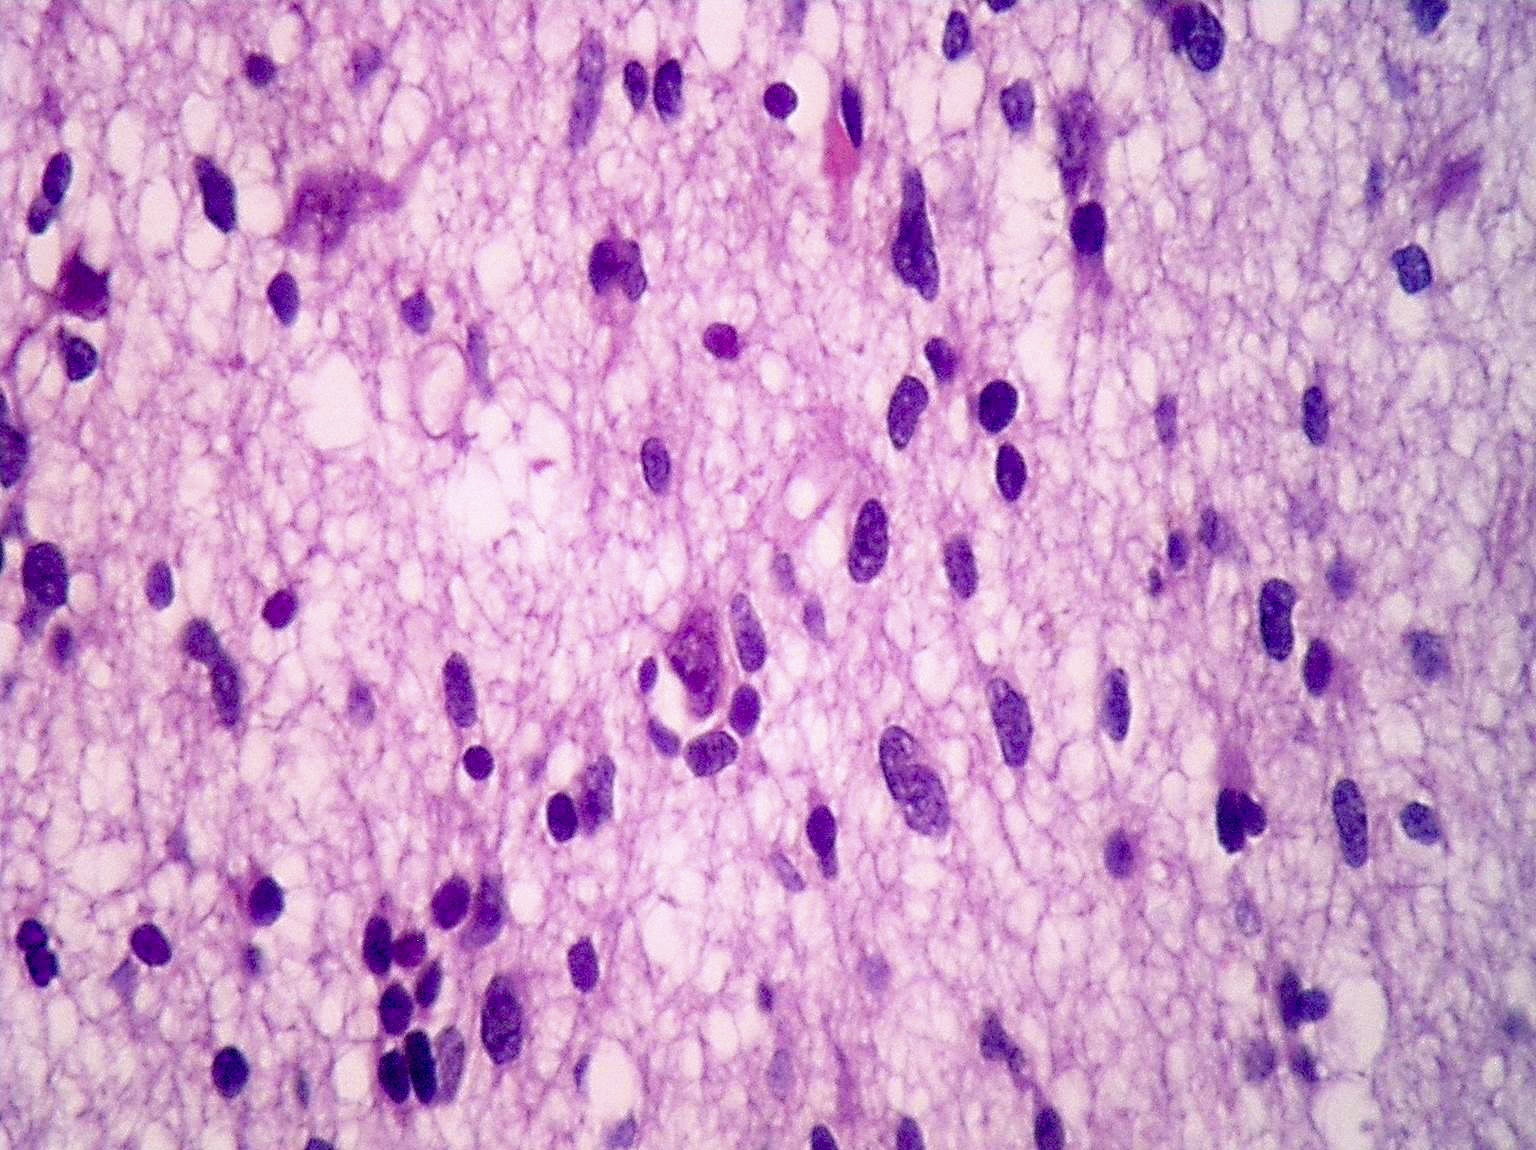

Микрофотографии гистологии глиобластомы головного мозга